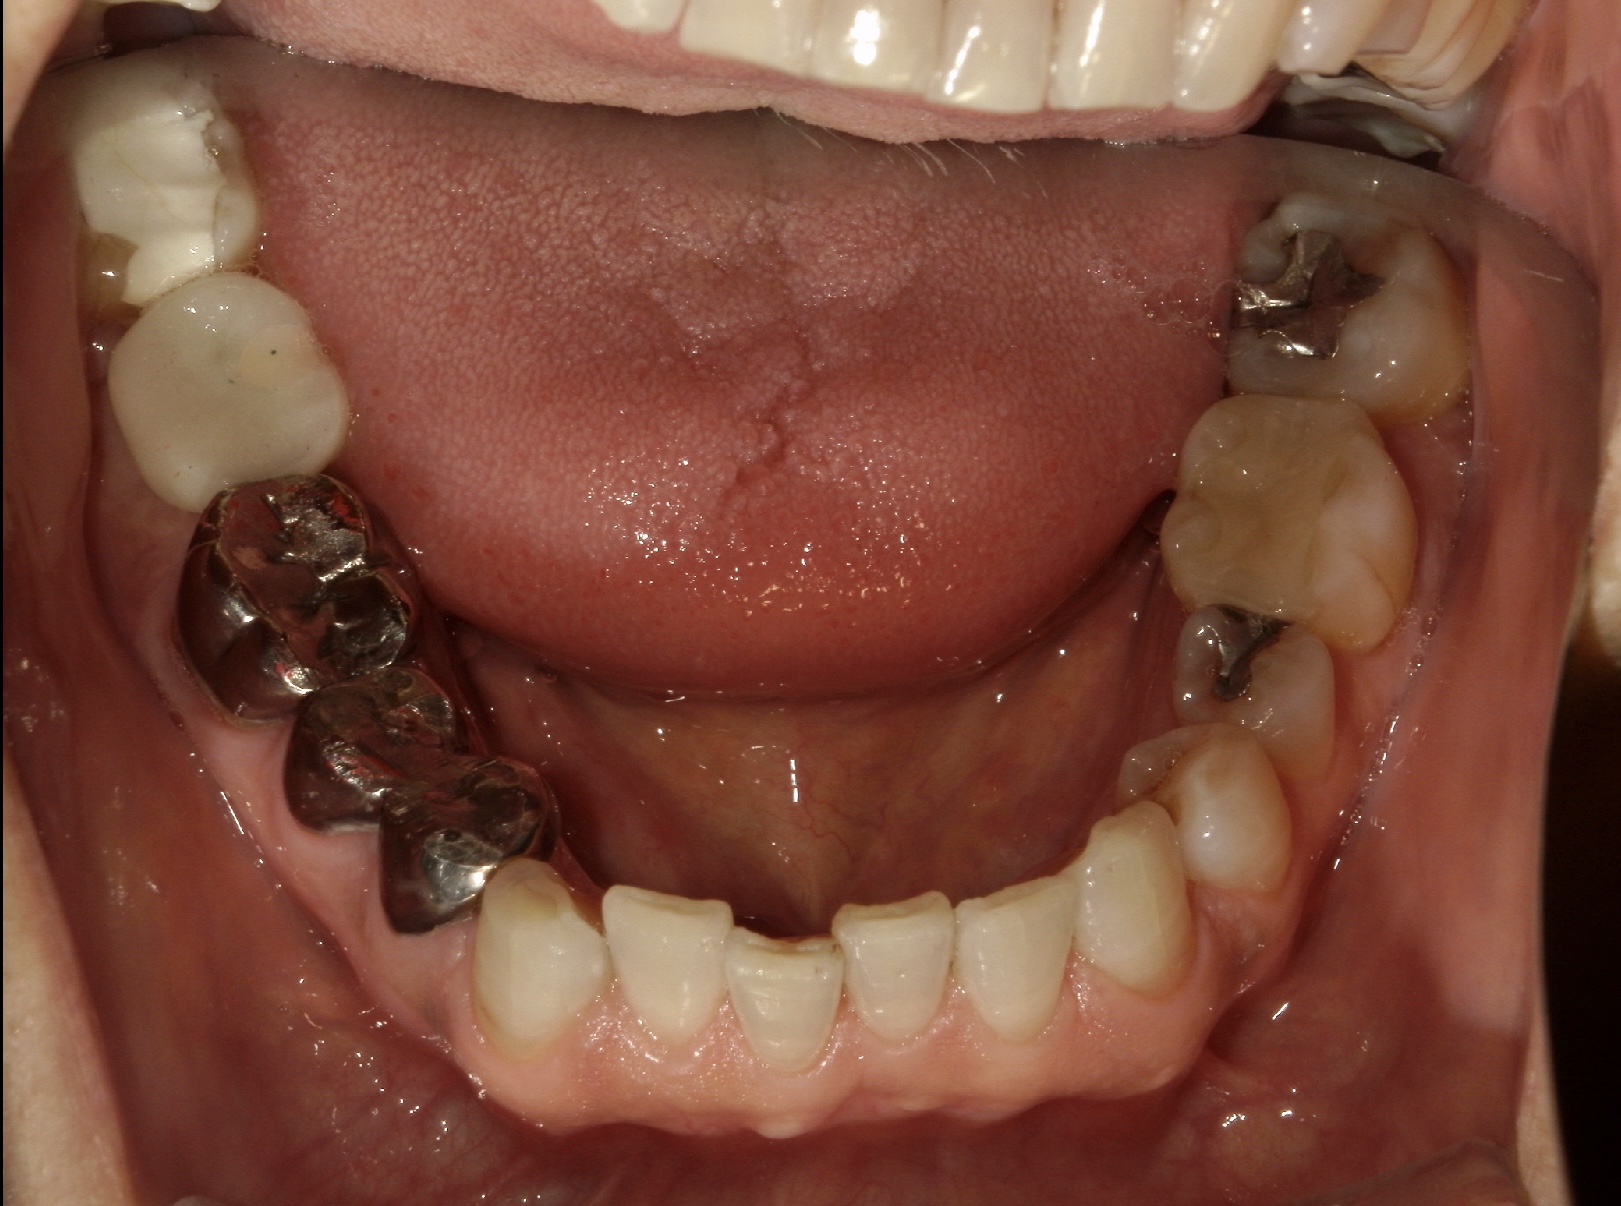

| 主訴 | 右下欠けたところがある。その他虫歯を治療したい |

| 年齢 | 60代女性 |

| 治療内容 | スクリューポスト不適合で、根尖病巣も大きく残すことが難しいため抜歯しインプラント治療へ。 歯槽骨の量が不足している場合に、人工骨や自家骨を移植し、特殊な膜で覆うことで骨の再生を促し、インプラントを埋入できるようにするGBRという治療法も併用。 |

| 抜歯部位 | 右下7 |